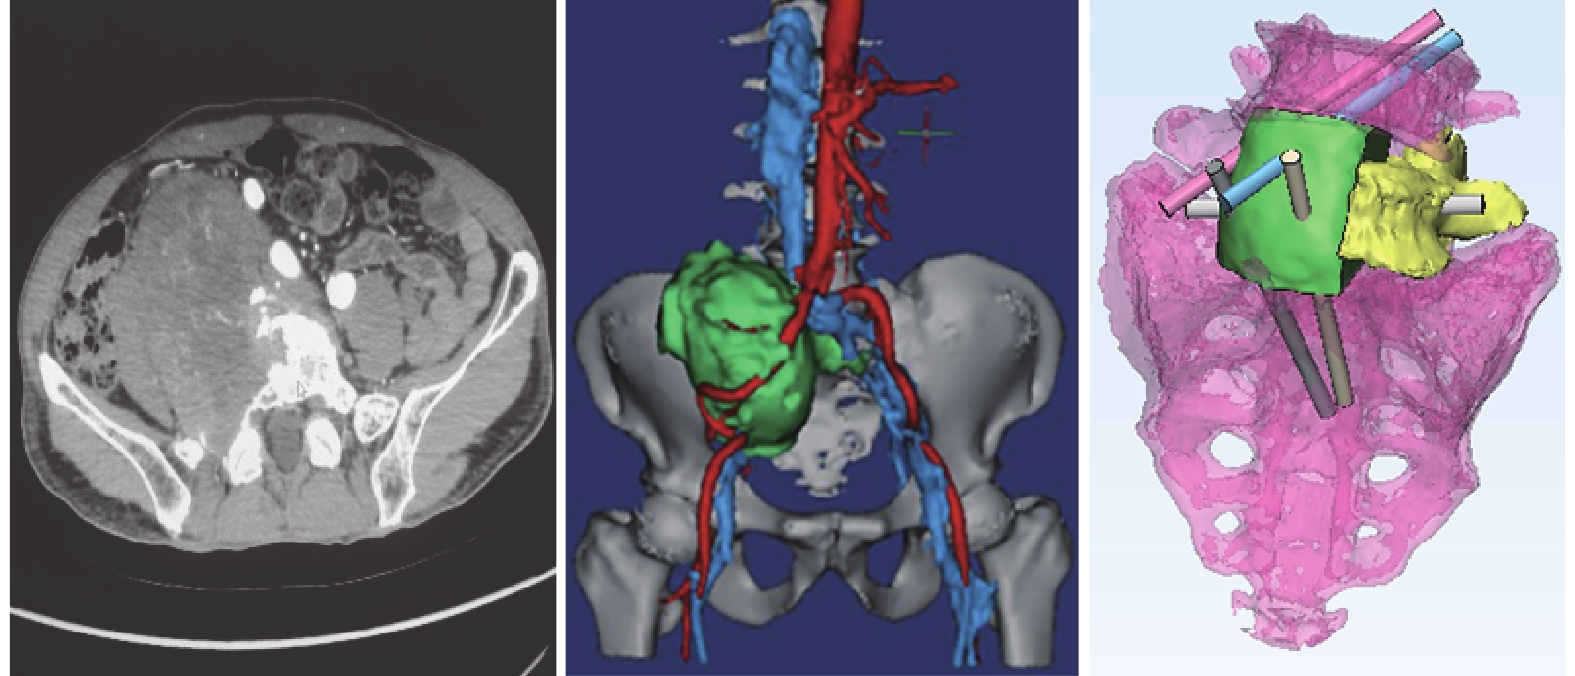

患者 男,66 歲。因查體時發現右下腹部占位 4 d 入院。檢查右下腹部有一拳頭大小包塊,無下肢麻木及放射痛。盆腔 CT 增強掃描顯示,脊柱腰骶部右側旁盆腔內見一 8.9 cm×7.8 cm×7.6 cm 大小的不均勻明顯強化腫塊,相鄰 L5、S1 椎體骨質破壞,破壞骨質邊緣呈壓跡狀輕度硬化,腫塊推壓對應右側輸尿管前移,右腎盂輕度擴張積水;CT 血管造影顯示,右側髂總、髂外、髂內動靜脈均被腫塊推壓向外前方移位,右髂內、外靜脈受壓明顯變細;腰骶尾椎 MRI 顯示,腫塊呈稍長 T1、長 T2 混雜信號,彌散加權像呈不均勻高信號,腫塊部分內側緣與 L5、S1 椎間孔關系密切。超聲引導下經皮穿刺行病理檢查考慮為神經鞘膜瘤。術前利用 Mimics 軟件處理 CT 掃描數據,模擬手術切除腫瘤,并設計 L5、S1 椎體模型,然后將椎體模型數據導入 3-D 金屬打印機,采用鈦合金(Ti6AL4V)按照 1∶1 比例打印實體椎體。見圖 1。